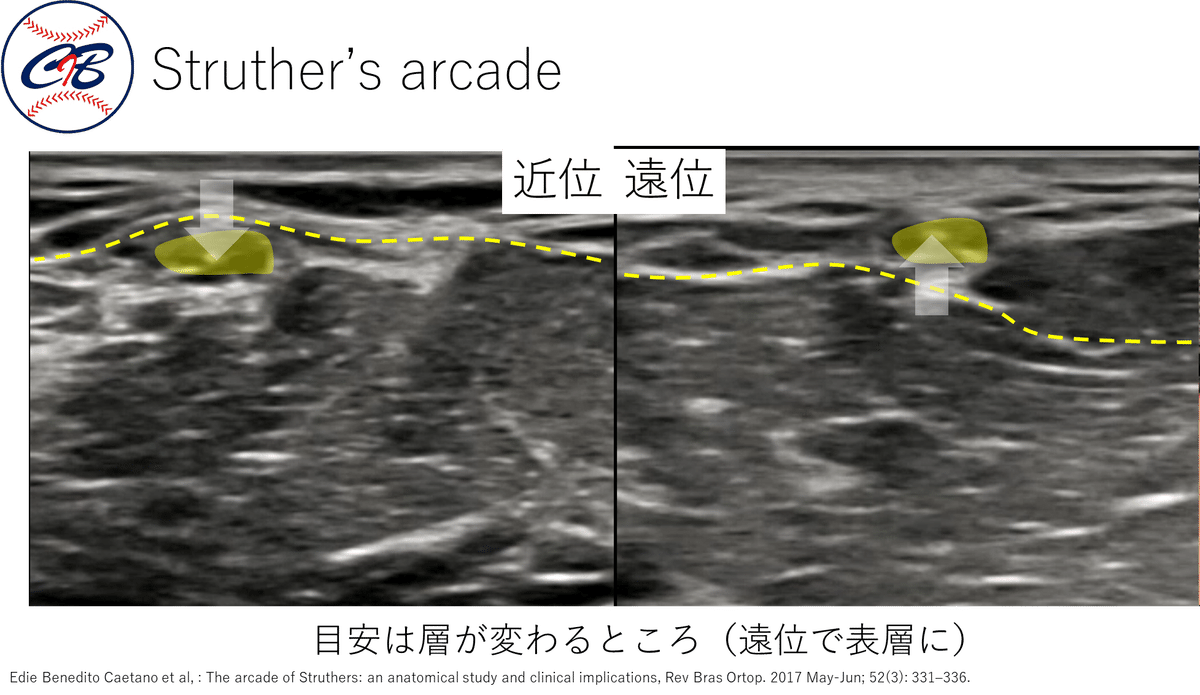

★各絞扼好発部位での Tinel sign~エコーでの見え方~

それぞれの部位がエコーでどのように診れるかを示していきます。